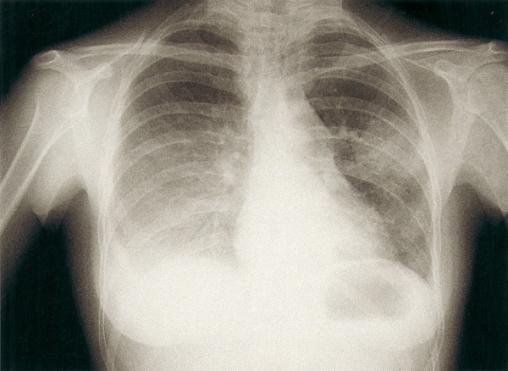

©La Revue du Praticien Radiographie de thorax de face. Pneumonie sévère bilatérale hypoxémiante à pneumocoque.